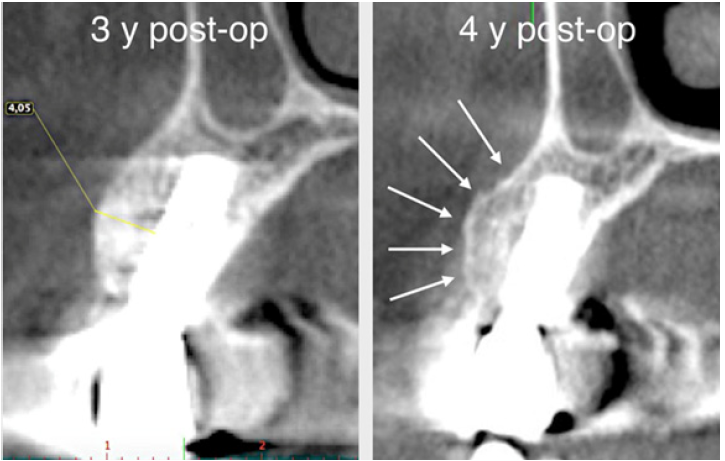

The surgery ended with 5/0 Polypropylene horizontal mattress sutures (Aragò, Barcelona, Spain). Amoxicillin 500mg every 8 hours for 7 days, Ibuprofen 600mgx3 for 3 days, Chlorhexidine 0.20% rinses morning and evening for 7 days were prescribed as postoperative medication. Postsurgical CBCT demonstrates a buccal augmentation of 4.05mm. The sutures were removed after 2 weeks of uneventful post-operative course (Figure 1-7). Six months after surgery, the clinical aspect showed an excellent volume of convex shape and hard consistency. The CBCT highlighted a horizontal gain of 4.05mm with initial mineralization. The day of re-entry the area displayed a new anatomy. The mesial implant was covered with hard tissue reproducing the shape of the cover-screw. A biopsy was taken and stored in 10% buffered neutral formalin and sent for histological examination. Healing abutments were connected and soft tissue sutured in place. After 3 months a prosthetic restoration was performed by means of a gold-ceramic screwed bridge. The histological result showed newly formed trabecular bone, in close contact with residual particles and osteoid matrix where newly formed blood vessels and active osteoblasts were present. There were not inflammatory or necrotic cells. Three years after surgery, the clinical and CBCT control show hard and soft tissue stability. The horizontal measurement of new vestibular bone is stable at 4.05mm. The peri-apical rx shows no marginal bone loss. Four years after surgery, a significant finding was observed on the new CBCT: the graft appeared almost totally reabsorbed in favor of new bone which has a radiological quality similar to that of the native bone and there is a new mature cortical plate [21] similar to the palatal native bone (Figure 8-15).

Figure 9: Horizontal increment of 4.05mm. Initial mineralization of newly formed bone (arrows).

Figure 13: Maintenance of horizontal gain (4.05mm). No bone loss at implant platforms.

Figure 14: Four year post-op the graft is almost completely resorb

Figure 15: The new cortical bone is comparable to that of native bone (arrows).